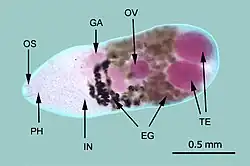

Metagonimus yokogawai, or the Yokogawa fluke, is a species of a trematode, or fluke worm, in the family Heterophyidae.

Metagonimus yokogawai has adult flukes that parasitize the small intestine and causes inflammation.[5] This species was discovered by Fujiro Katsurada with egg samples from Japan and Taiwan [6] With this discovery, he was able to make a new genus of trematodes that this new parasite would fall under [6] The size of these eggs are about 29 μm.[7] Evidence also suggest that this parasite was present during the Yi dynasty.